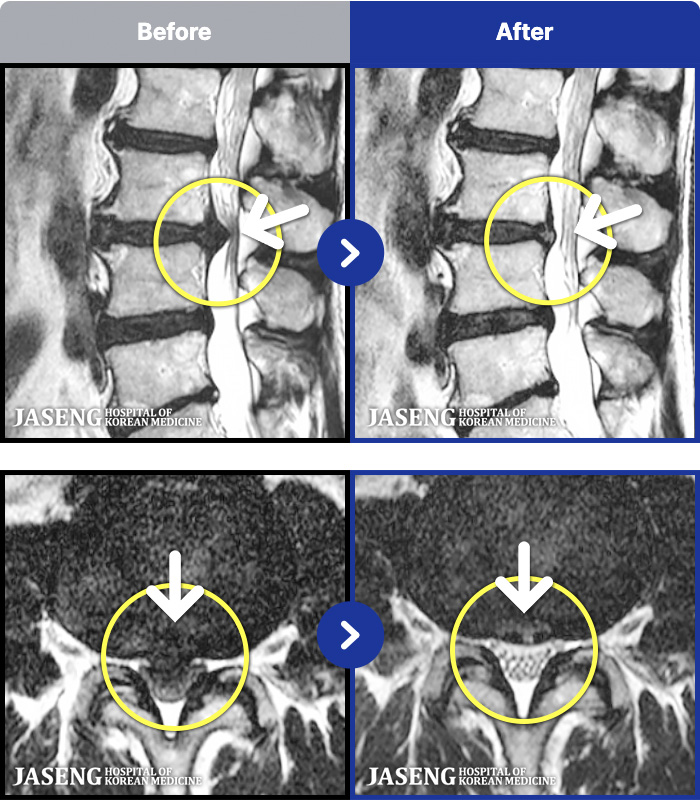

MRI ġ

1,304 MRI ũ ʸ Ȯϼ.